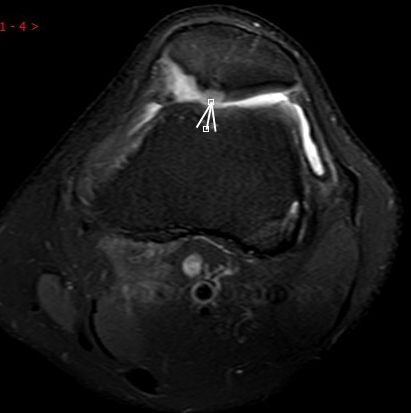

3. 上下樓“針刺痛”——軟骨的“磨砂紙預(yù)警”

場景:爬樓梯時膝蓋刺痛,久坐后僵硬如“生銹齒輪”

MRI偵查:發(fā)現(xiàn)軟骨變薄、缺損(早期骨關(guān)節(jié)炎信號),趕在“路面塌方”前修復(fù)

(軟骨損傷)